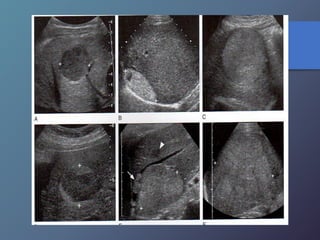

Metástasis

• Su incidencia depende del tipo de tumor.

• Localizaciones mas frecuentes del TU primario:

vesícula biliar, colon, estomago, páncreas, mama y

pulmón.

• Pueden presentar una sola lesión hepática, aunque

suelen tener múltiples masas focales.

Mt Hiperecoicas

• Ecográficamente se presentan las lesiones

de tamaño variable con presencia de un

halo hipoecoico.

• Diferenciar lesiones malignas de benignas

por presencia de halo hipoecoico.

• Se describen como lesiones ecógenas,

hipoecoicas, en diana, calcificadas,

quísticas y difusas.

Clasificación de las Metástasis

Metástasis • Su incidenciadepende del tipo de tumor. • Localizaciones mas frecuentes del TU primario: vesícula biliar, colon, estomago, páncreas, mama y pulmón. • Pueden presentar una sola lesión hepática, aunque suelen tener múltiples masas focales. Mt Hiperecoicas

• Ecográficamente sepresentan las lesiones de tamaño variable con presencia de un halo hipoecoico. • Diferenciar lesiones malignas de benignas por presencia de halo hipoecoico. • Se describen como lesiones ecógenas, hipoecoicas, en diana, calcificadas, quísticas y difusas.

Clasificación de lasMetástasis MT ecogenas: • origen digestivo o chc. MT hipoecoicas: • Son hipovasculares. • Origen CA de mamas, pulmón, páncreas y esófago. • Los linfomas hepáticos pueden manifestarse en masas hipoecoicas, o difusas difíciles de diferenciar por ecografía o TC. MT en diana: • Presentan una zona hipoecoica periférica, con centro hiperecoico. • Frecuente en carcinomas broncogenos.

MT calcificadas: • Presentanuna ecogenicidad acentuada y marcada sombra Acústica • Frecuentes en adenocarcinoma de colon, gástricos, TU. Pancreaticos, leiomiosarcomas, neuroblastomas, cistadenocarcinomas, teratocarcinoma ováricos. MT quísticas: • Son poco frecuentes • Son de paredes muy gruesas, presencia de tabiques internos, ecos de nivel bajo. • Pueden observarse en el cistadenocarcinoma del ovario y del páncreas y en el carcinoma mucinoso de colon.